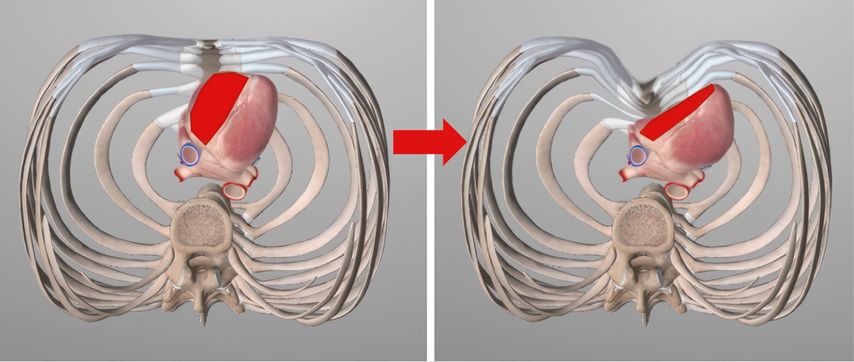

In mittel- bis höhergradigen Fällen kommt es im Zuge des zunehmenden Mediastinalshifts zu einer Linksverlagerung sowie auch einer Kompression des Herzens, wo mechanisch vor allem das rechte Kammersystem betroffen ist.6,7Der rechte Ventrikel ist eingeengt, verliert an Compliance und nimmt in der radiologischen Darstellung eine „tubuläre Form“ an. Damit sinkt auch die „ejection fraction“ und damit insgesamt der „cardiac output“ (Abb.2). Eine Situation, die therapeutisch nachweislich verbessert werden kann.8